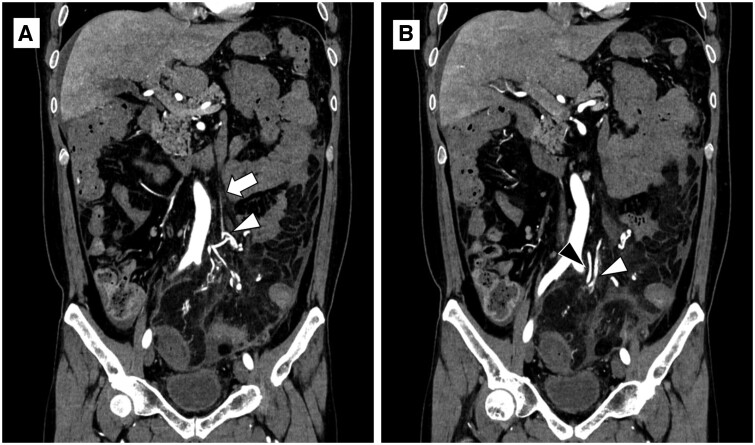

A 44-year-old man presented with a chief complaint of constipation. Initial contrast-enhanced CT showed extensive bowel wall thickening, mainly in the left colon, with a thin cord-like inferior mesenteric vein (IMV), in contrast to ectatic mesenteric venous branches, suggesting bowel ischaemia owing to venous stasis. One month later, at the time of symptom exacerbation, CT angiography showed a cord-like IMV and ectatic mesenteric venous branches with early enhancement, suggesting the presence of an arteriovenous fistula (AVF). Owing to the progression of bowel ischaemia and necrosis with peritonitis, emergency surgery was performed. Surgical specimens showed focal myointimal hyperplasia of the proximal mesenteric veins in both ischaemic and non-ischaemic lesions of the resected colon, thus leading to the diagnosis of idiopathic myointimal hyperplasia of mesenteric veins (IMHMV) when combined with the clinical and imaging findings. IMHMV is a bowel ischaemic disease caused by non-thrombotic venous obstruction that requires bowel resection and has been suggested to be associated with AVF. Cord-like IMV and AVF in the mesentery are important CT findings that characterize IMHMV. CT angiography is useful in diagnosing IMHMV.

一名 44 岁男子以便秘为主诉就诊。最初的造影剂增强 CT 显示肠壁广泛增厚,主要位于左侧结肠,肠系膜下静脉(IMV)呈细绳状,肠系膜静脉分支异位,表明由于静脉瘀血导致肠缺血。一个月后,症状加重时,CT 血管造影显示肠系膜下静脉(IMV)呈条索状,肠系膜静脉分支异位且早期增强,提示存在动静脉瘘(AVF)。由于肠道缺血坏死并伴有腹膜炎,医生对患者进行了紧急手术。手术标本显示,在切除的结肠缺血和非缺血病灶中,肠系膜近端静脉均有局灶性肌腱增生,因此结合临床和影像学检查结果,诊断为特发性肠系膜静脉肌腱增生症(IMHMV)。IMHMV是一种由非血栓性静脉阻塞引起的肠缺血性疾病,需要切除肠道,并被认为与动静脉瘘有关。索状 IMV 和肠系膜中的动静脉瘘是 IMHMV 的重要 CT 发现特征。CT 血管造影有助于诊断 IMHMV。